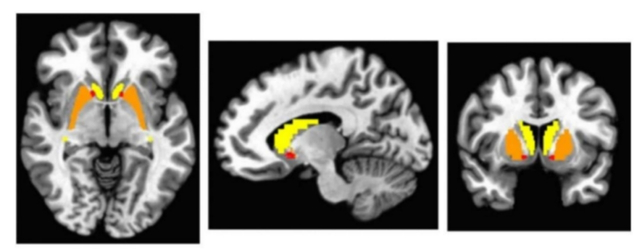

Areas of the brain scanned based on unusual connections in autism thought to be related to DA signaling (Nuraini et al., Autism Res., 2025).